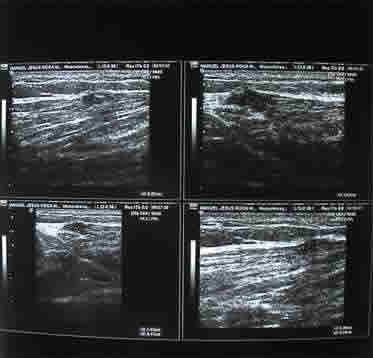

Se le realiza Ecografía en el Hospital y esta nos confirma

el diagnóstico.